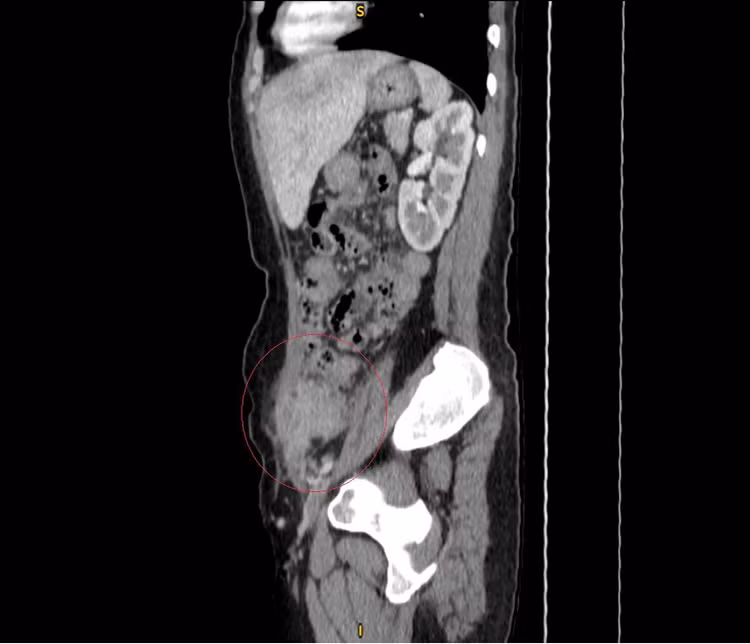

Tại Khoa Ngoại Tổng quát Bệnh viện Đa khoa Xuyên Á, các bác sĩ thăm khám sờ thấy khối sưng đau vùng hố chậu trái kích thước 4cm. Chụp CT - scanner phát hiện áp xe thành bụng, nội soi đại tràng ghi nhận sẹo loét trực tràng.

Người bệnh được chẩn đoán thủng túi thừa đại tràng sigma rò ra ngoài thành bụng kết hợp rò trực tràng - âm đạo, đây được đánh giá là trường hợp hiếm gặp.

| Hình ảnh rò túi thừa trên phim chụp - Ảnh BVCC |